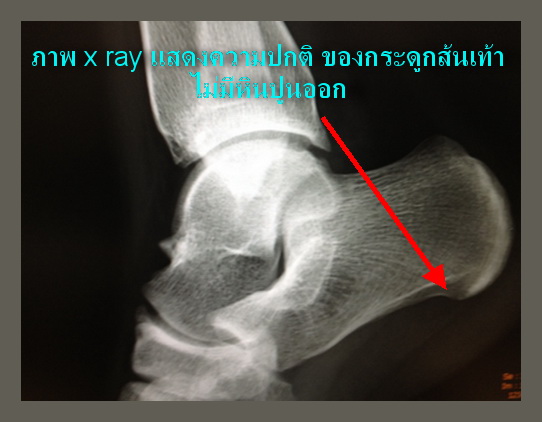

ในบางคนที่ปล่อยให้เป็นอยู่นานก็อาจจจะเกิดหินปูนเข้าไปเกาะที่กระดูกส้นเท้านั้น ทำให้เวลาเดิน จะมีเหมือนหนามแหลมเข้าไปทิ่มตำที่ส้นเท้าตลอดเวลา และถ้าหินปูนหนาและยาวมากขึ้น จนการรักษาวิธีอื่นไม่ได้ผล ก็จำเป็นต้องรักษาโดยการผ่าตัดและใช้เรื่องมือกรอหินปูนเพื่อเอาหินปูนออกเท่านั้น